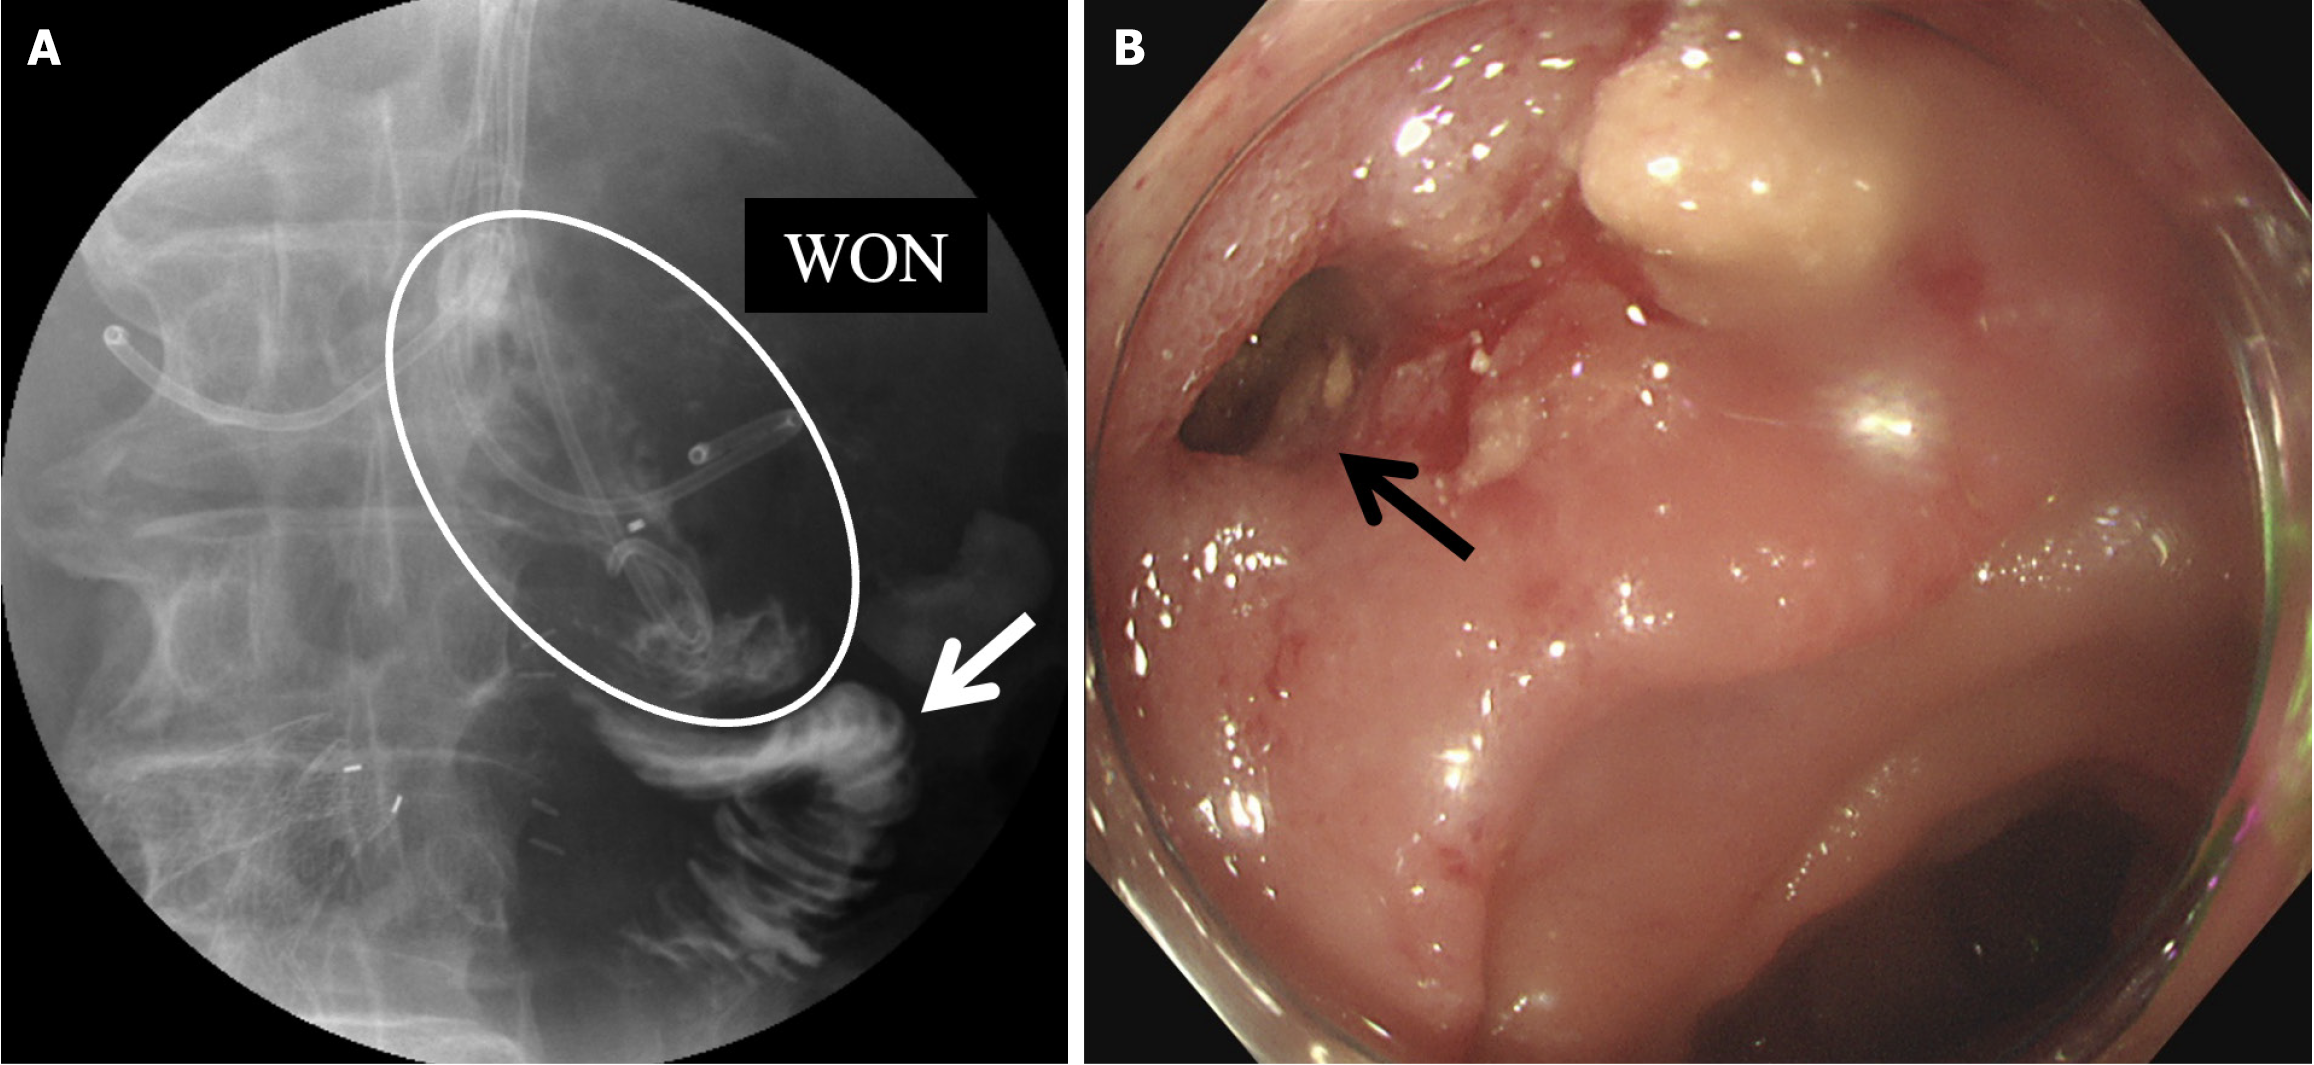

Figure 5 Image examination proved the fistula between walled-off necrosis and the duodenum.

A: The upper gastrointestinal tract contrast study showing a fistula between the walled-off necrosis (white circle) and duodenum (white arrow); B: Endoscopy showing the position of the fistula (black arrow). WON: Walled-off necrosis.